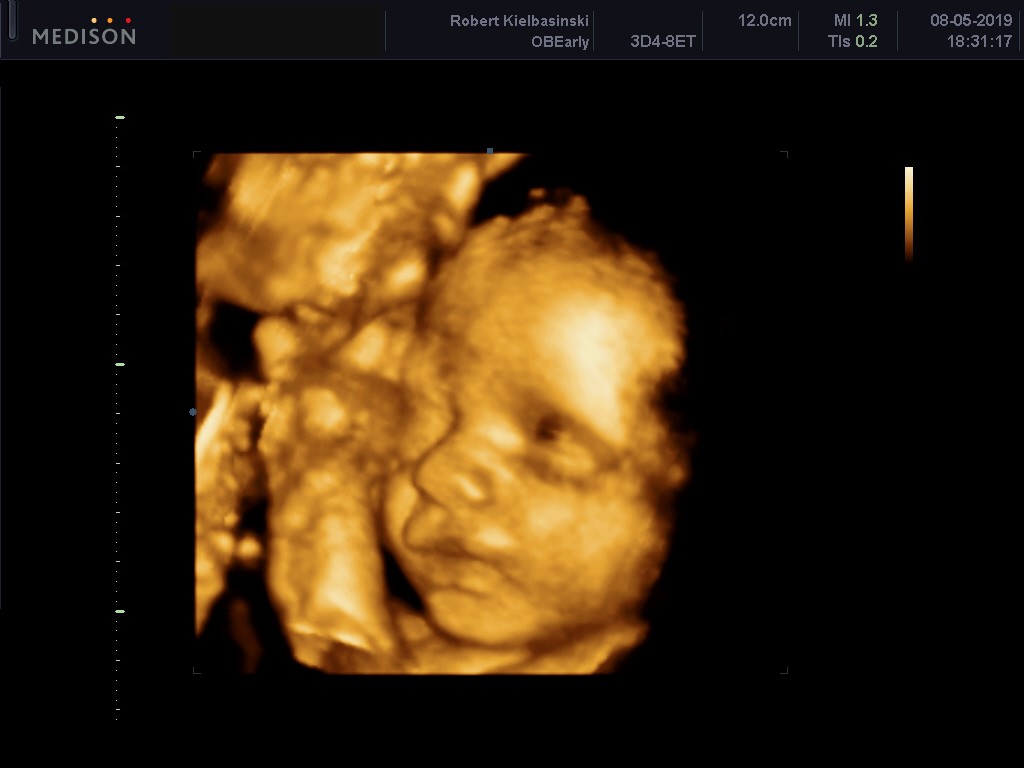

Aleksander to silny chłopak z wagą 1866g, termin z USG nadal 01.07.2019 i lekarz stwierdził, że raczej będzie lipcowym niż czerwcowym dzieckiem.

Malutki dzisiaj mocno dokazywał podczas USG i tak kopał, że aż lekarz był w szoku, że tak mocno potrafi.

Ps. Jestem zakochana w tym słodkim pysiaczku <3

Zobacz załącznik 970418